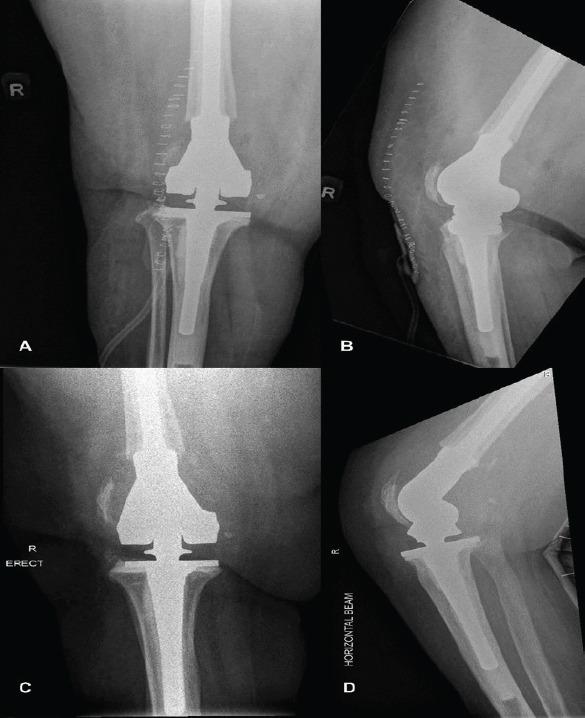

We present a case of a 64-year-old female of Southeast Asian descent who had a cement spacer maintained in-situ for 7 years due to poor patient compliance with subsequent follow-up.

While patients have satisfactory functional outcomes with the cement spacer, it is not meant for permanent weight bearing. Two-stage revision arthroplasties are only as effective as patients' compliance with subsequent follow-up and surgery. Clinicians must discourage patients from forgoing subsequent follow-up visits and surgery despite satisfactory function and quality of life with the cement spacer in situ to prevent complications related to prolonged retention of cement spacers.